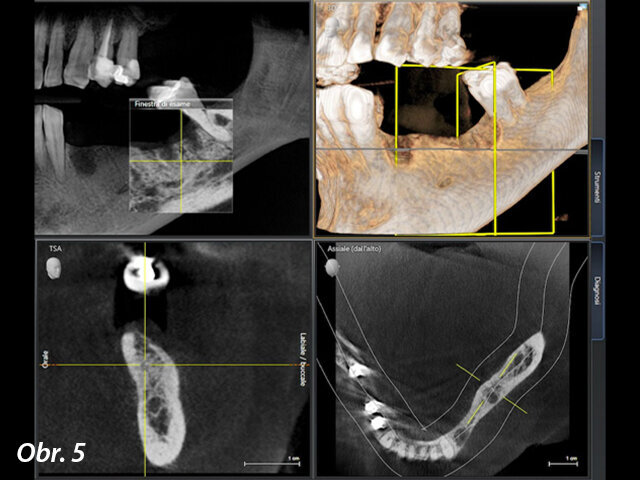

V místech zubů 34 a 36 byla naplánována fixní náhrada nesená implantáty. Z tohoto důvodu bylo provedeno vyšetření pomocí CBCT, které mělo pomoci posoudit kvalitu a kvantitu kosti pro zavedení implantátu (obr. 4, 5). Byl shledán dostatek vertikální kosti v obou místech, nicméně v oblasti zubu 34 bylo pro zavedení implantátu nedostatečné horizontální množství kosti. V této lokalitě byla tedy spolu se zavedením implantátu naplánována augmentace kosti pomocí xenoštěpu a kolagenní membrány a keramický vhojovací abutment.